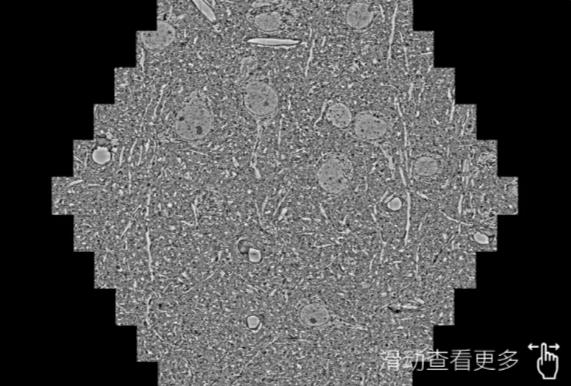

鼠脑切片。左图使用云阳蔡司云阳扫描电镜MultiSEM706对165μmx143pm面积区域成像,耗时仅需1.5秒。右图为鼠脑切片中30μm区域放大效果。样品由芝加哥大学B.Kasthuri提供。